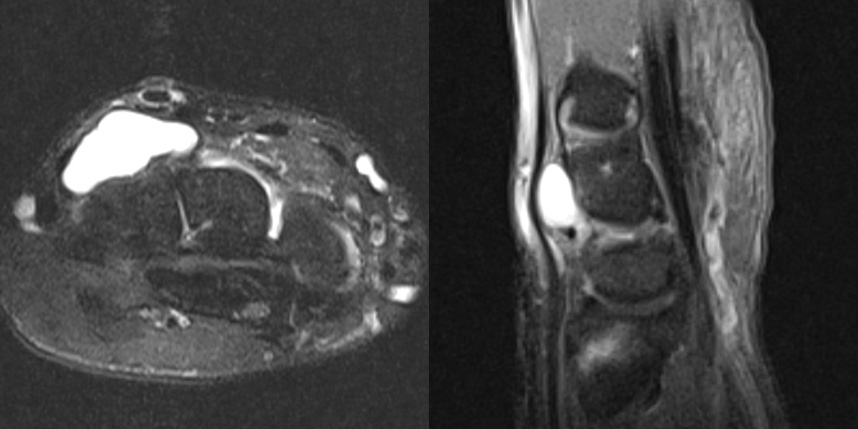

손목 앞쪽의 결절종이 있었지만, 뿌리는 손등쪽하고 연결된 까다로운 경우의 MRI 입니다.

만약 MRI 를 찍지 않았다면 손목 앞쪽에 보이는 결절종만 제거하여 재발 가능성이 높을 수 있는 경우입니다.

이 환자의 경우 앞, 뒤에 절개를 넣어 뿌리까지 제거해주어 재발 없이 유지되었습니다.

* 환자에게 받은 소중한 자료입니다.